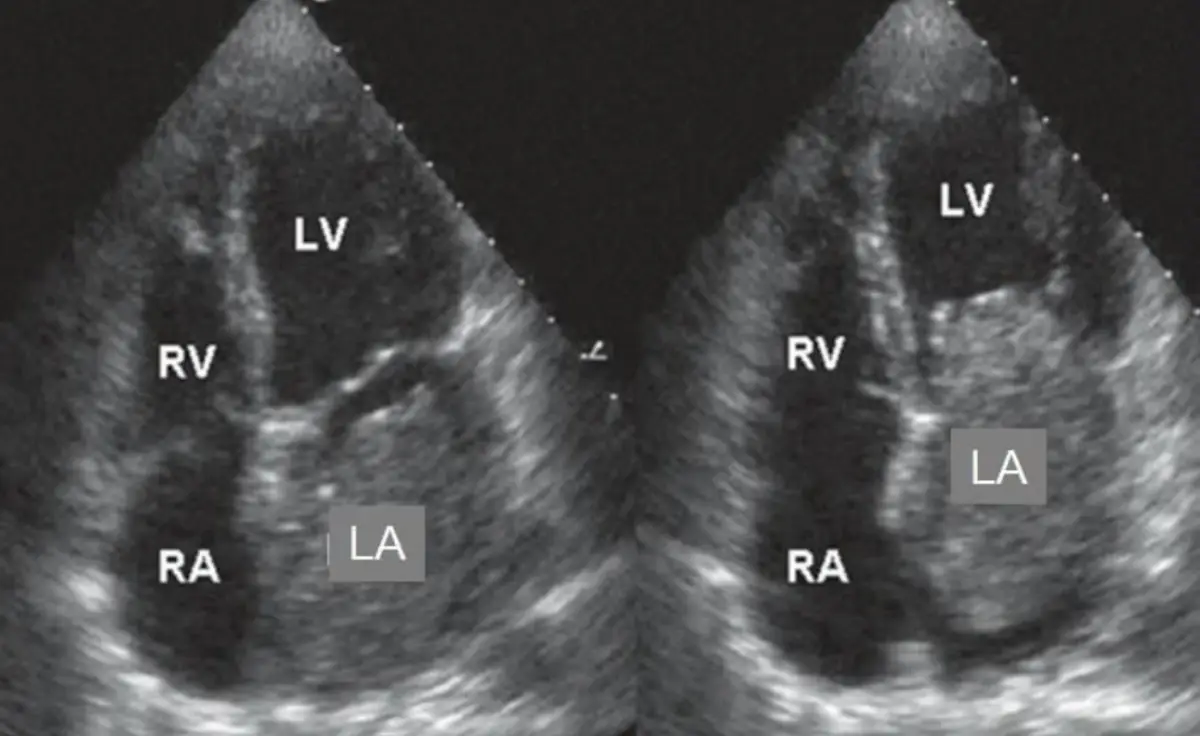

一位46歲女性病患呈現昏厥來門診求診,該症狀與特定姿勢有關.心臟超音波檢查如(附圖),左圖為心室收縮二尖瓣關閉時,右圖為心室舒張時圖像.有關敘述,下列何者錯誤?

從心臟超音波四腔切面可見一枚位於左心房 (LA) 的懸蒂狀腫瘤 (pedunculated mass),左圖於心室收縮(二尖瓣已關閉)時,腫瘤仍留在左心房;右圖於心室舒張(二尖瓣開啟)時,腫瘤明顯從左心房脫垂至二尖瓣環,並部分進入左心室 (LV);此現象典型於左心房黏液瘤,解釋了因體位改變而造成二尖瓣口動態阻塞與暫時性灌注不足所致的昏厥。